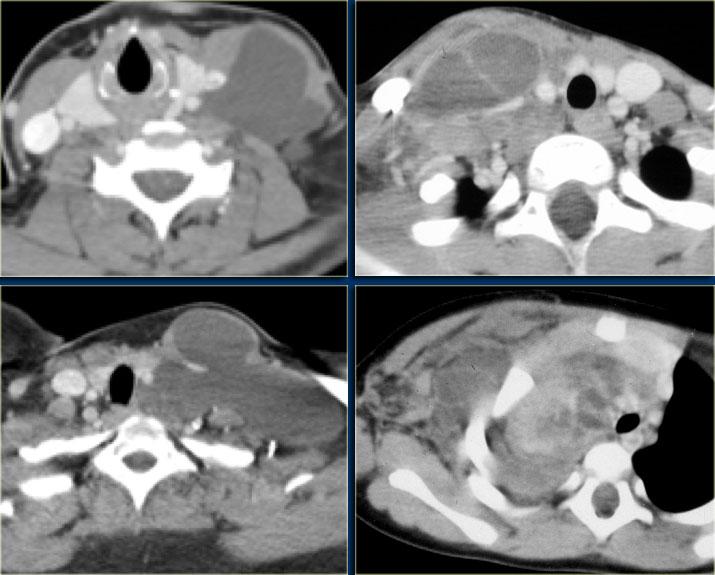

Các hình ảnh cho thấy u tuyến ức ở bên trái và ung thư biểu mô ở bên phải.

Ung thư biểu mô tuyến ức đã xâm lấn tĩnh mạch chủ trên (mũi tên).